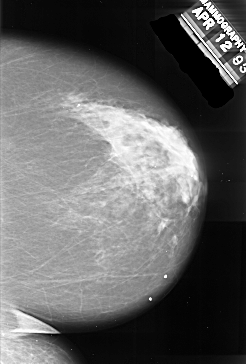

A_1017_1.LEFT_MLO

DATE_OF_STUDY 12 4 1993

PATIENT_AGE 76

FILM_TYPE REGULAR

DENSITY 4

LEFT_MLO LINES 5866 PIXELS_PER_LINE 3466 BITS_PER_PIXEL 16 RESOLUTION 42 OVERLAY